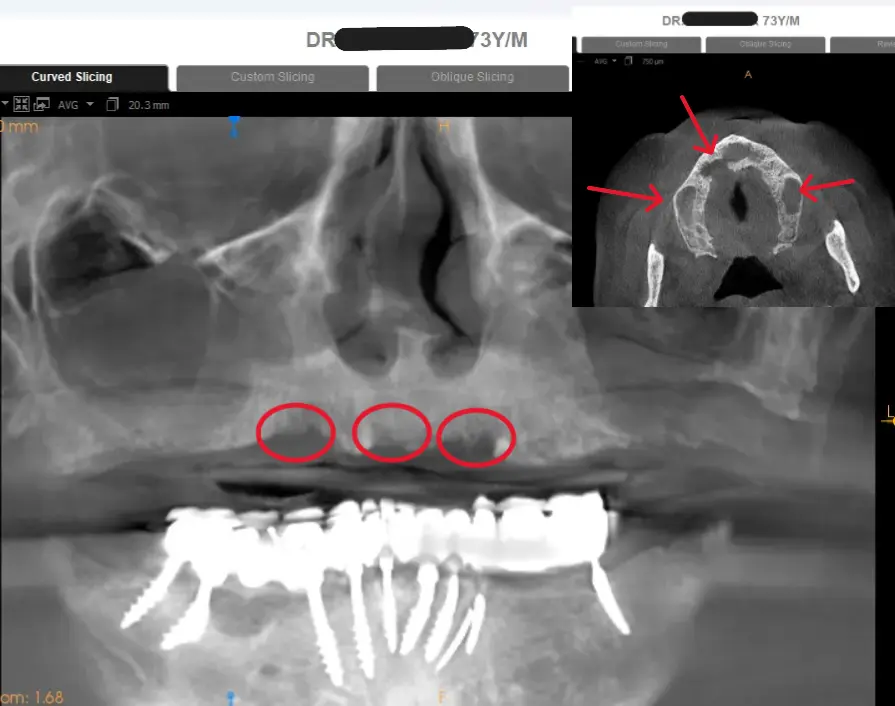

A famous Delhi doctor went for basal implants hoping for “teeth in a week.” Six months later — infection, pain, and massive bone loss. The implants couldn’t even be removed easily; they weren’t FDA approved or retrievable. When no clinic in Delhi NCR took the case, Dr Jyoti Singh at the Center for Dental Implants & Esthetics, Gurgaon rebuilt his jaw with 3D-guided All-on-4 implants. One surgery. Full recovery. Real science, not shortcuts. .

Failed basal implants after 6 months—severe infection, single piece implant resulted in bite misalignment space for food to go under dentures infection, bone loss implant visible

Severe bone destruction seen marked red in upper jaw during basal implant removal—irreversible damage and extremely painful procedure for 72 yr old

USFDA-approved All-on-4 implants placed with 3D planning & surgical guides, and proper osseointegration protocol